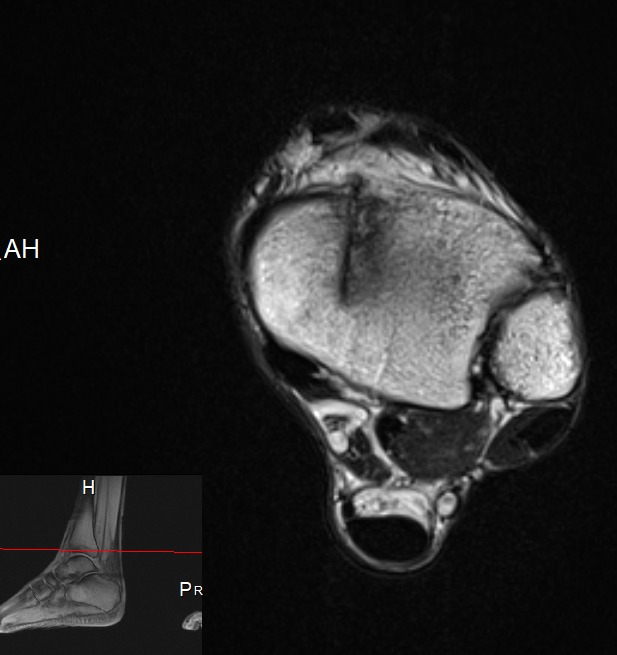

Helen has the first Focus Shockwave Therapy Duolith in Scotland The Focus Shockwave Therapy is extremely useful for chronic tendinopathies such as Tennis Elbow, Achilles Tendinopathy and Helen is delighted with having excellent success with chronic back stiffness and spasms You can read the indications for Focus Shockwave Therapy by scrolling down the page as this is a wider range than one would expect Shockwave Therapy is always to be used as an adjunct to good quality continual professional courses which provide evidence based rehabilitation and management

A recent Article in the The Courier It is important to know that Helen is using Focused Shockwaves and not Radial Shockwaves which is the most common form of shockwaves therapy used in 95% of the MKS Clinics